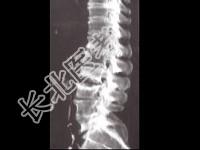

- 单项选择题男,65岁, 腰背部疼痛1月余,结合图像, 最可能的诊断是 ( )

A、脊椎结核

B、椎体压缩骨折

C、脊椎退行性变

D、脊椎转移瘤

E、L2~L3椎间盘炎